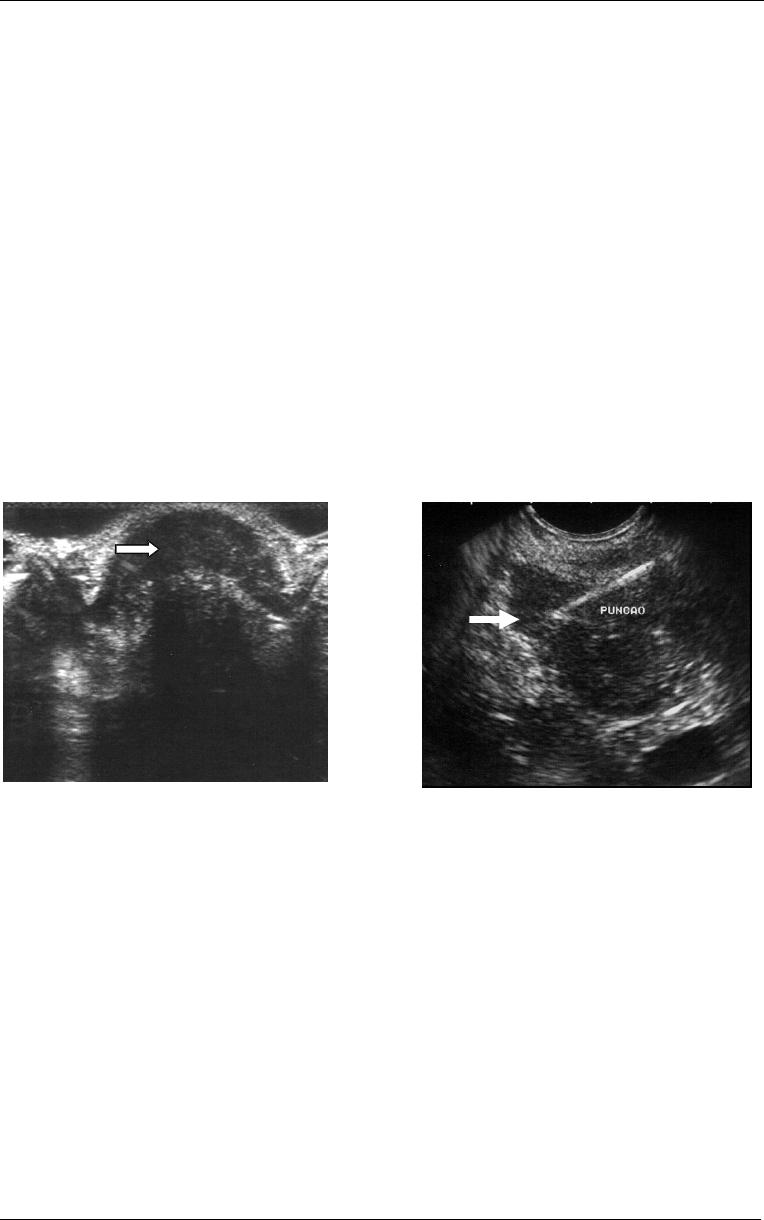

Figura

9

- Imagem de

ressonância magnética em corte

sagital evidenciando

deformidade e espessamento do

reto (seta) decorrente de

endometriose intestinal. Obs:

Imagem cedida pelo Dr. Dario

Tíferes do Laboratório de

Análises Clínicas Gastão Fleury

S/C Ltda.

10

- Imagem de ressonância magnética

em corte axial, evidenciando espessamento do

reto (seta) decorrente de endometriose

intestinal. Obs: Imagem cedida pelo Dr. Dario

Tíferes do Laboratório de Análises Clínicas

Gastão Fleury S/C Ltda.

O método proporciona detalhes da parede intestinal e de estruturas ao redor

da mesma, superáveis apenas pelo exame histológico, sendo considerado o melhor

exame para a determinação do grau de invasão de lesões na parede intestinal,

informação importante na determinação pré-operatória do tipo de ressecção a ser

realizada (Van Dam, Sivak Jr, 1999, Chapron et al 2004) (Figura 11).